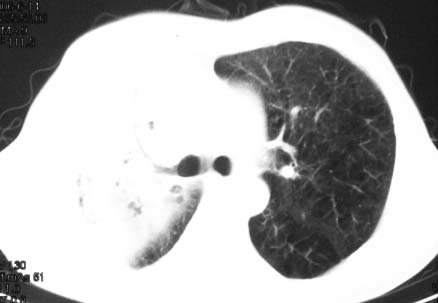

影象表现:右肺上叶大片状、网格状及索条致密影,蜂窝影,其内参杂斑点状小结节,密度不均匀,内见含气支气管像,纵隔内见肿大淋巴结.

抗感染病变无明显改善,右上叶大片状增弥不均匀病灶,夹杂网状及支气管充气像,肺门纵隔淋巴结肿大,右侧胸腔积液。考虑1混合感染伴肺间质改变[警惕特殊感染,如真菌]。2细支气管肺泡癌。建议结合临床及进一步检查[如痰,胸水脱落细胞检查及支气管镜检灌洗或穿刺活检

影象表现:右肺上叶大片状、网格状及索条致密影,蜂窝影,其内参杂斑点状小结节,密度不均匀,内见枯枝样含气支气管像,纵隔内见肿大淋巴结.胸膜广泛增厚,前胸壁似受累.少量胸腔积液.纵隔内淋巴结的直径>1.5cm.右侧胸廓体积缩小.考虑:1 肺结核合并间质纤维化 2 细支气管肺泡癌

右肺上叶大片状、网格状及索条致密影,蜂窝影,其内参杂斑点状小结节,密度不均匀,内见枯枝样含气支气管像,纵隔内见肿大淋巴结.胸膜广泛增厚,前胸壁受累增厚.少量胸腔积液.纵隔内淋巴结的直径>1.5cm.右侧胸廓体积缩小.考虑: 细支气管肺泡癌并肺内癌性淋巴管炎。